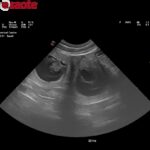

| Zdraví | DKK: 0/0 (A), DLK: 0/0 (RTG CZ 2021, Mvdr. Slabý) MDR1 +/+, DM n/n, OCD n/n, Baer +/+, LTV normální, SA 0 – negativní, FGF5 n/n (nese pouze krátkosrstý gen), MH n/n, DNA |